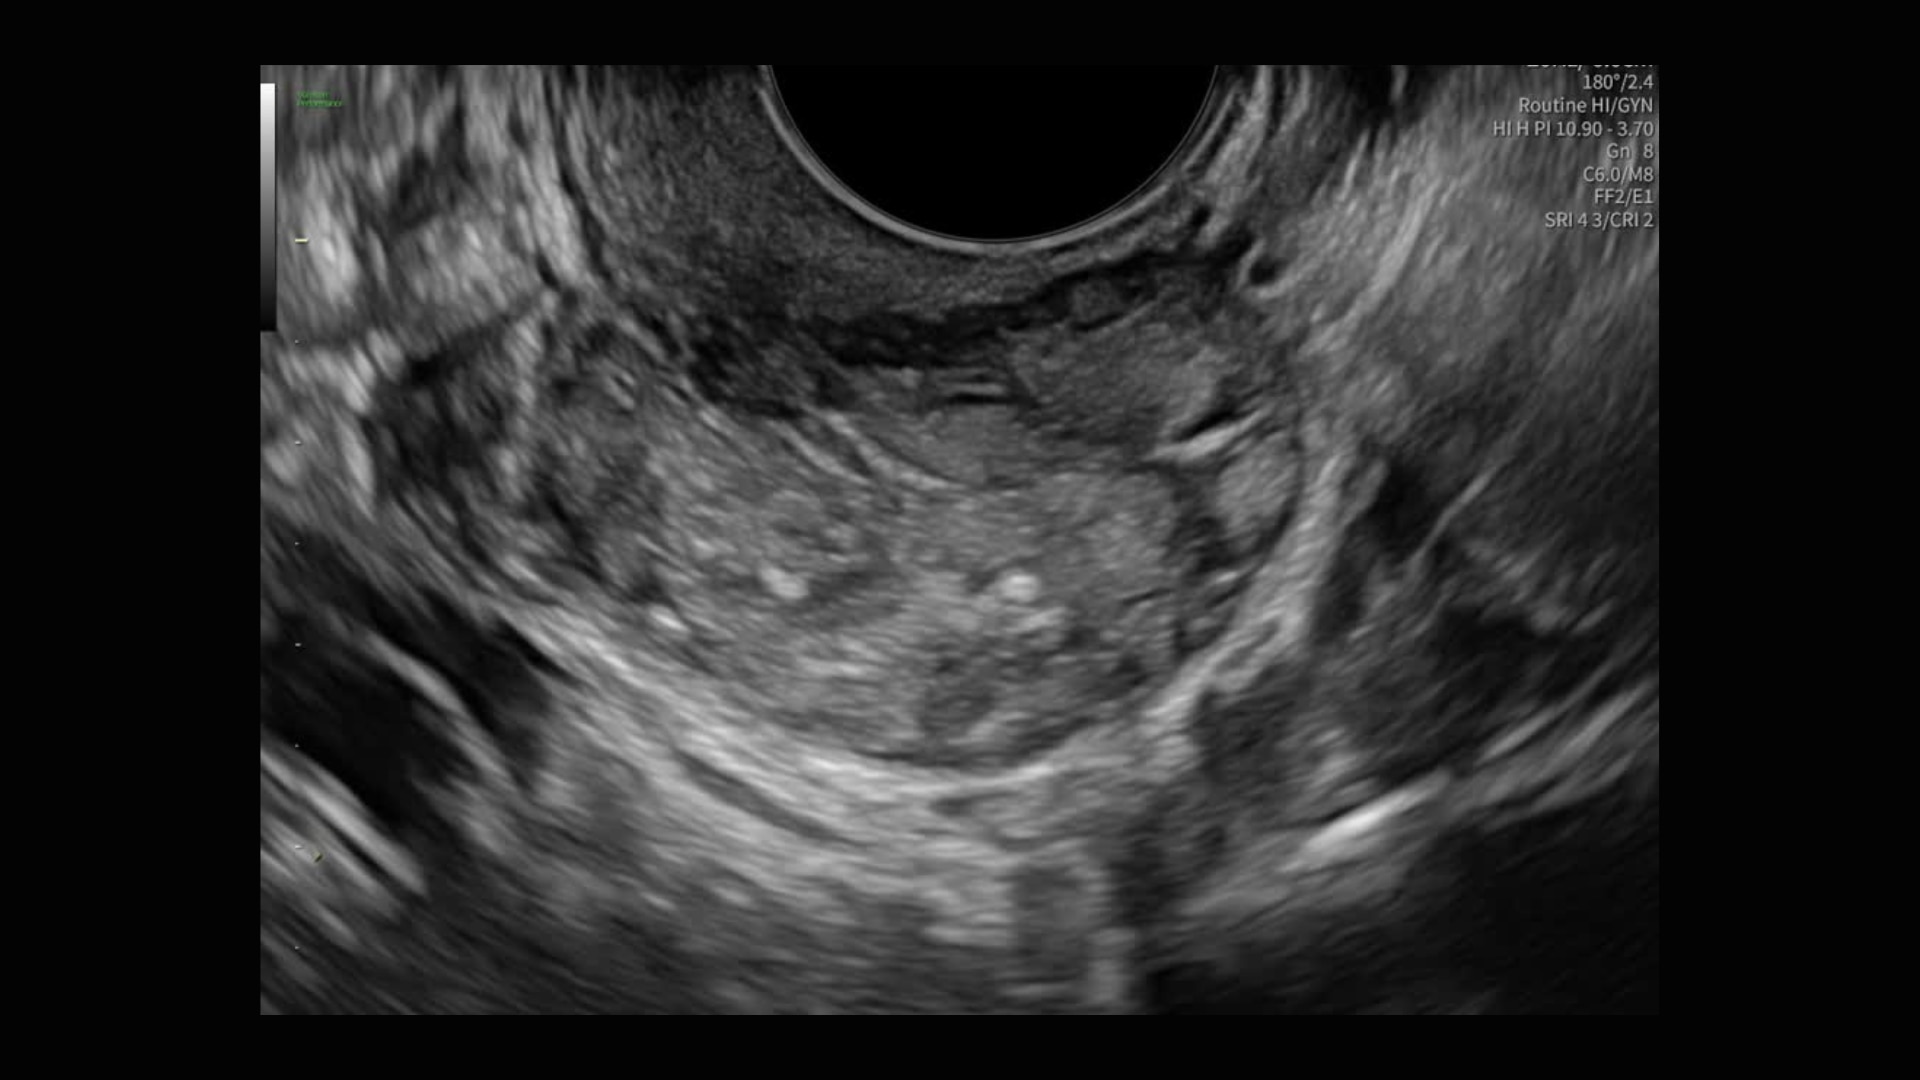

Radiantflow™

Fast, easy 3D-like blood flow visualization

Radiantflow delivers exceptionally sensitive, next level color Doppler for easy fast visualization of blood flow revealing even the tiniest vessels.